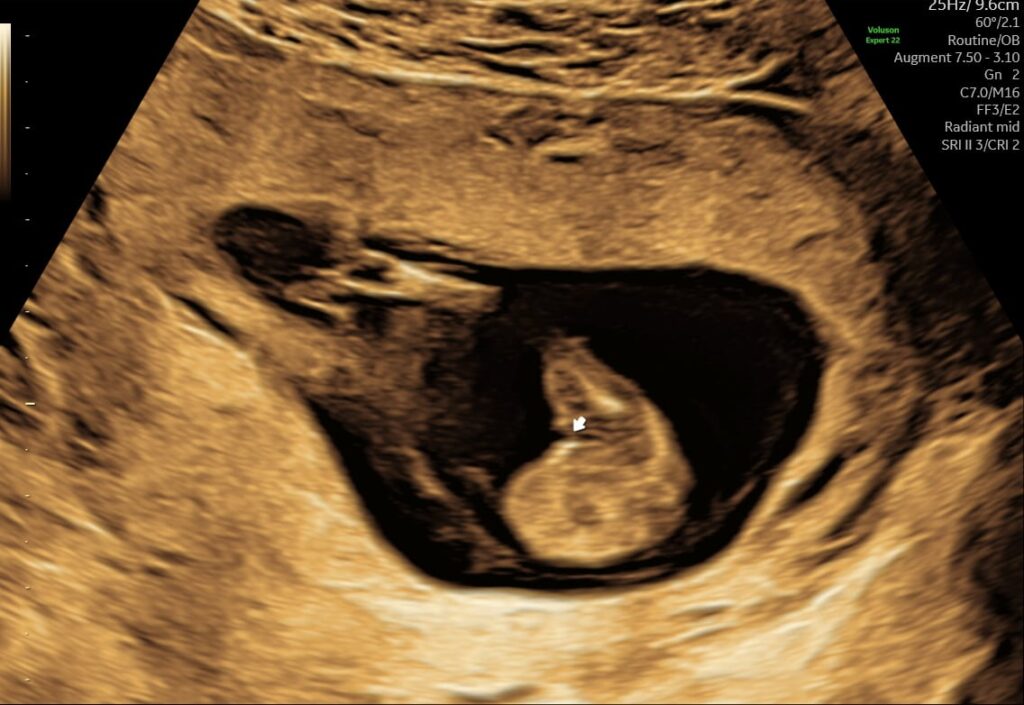

Mange kommende forældre glæder sig til at få at vide, om det er en lille dreng eller pige, der er på vej. Allerede fra uge 14+0 kan vi med en kønsscanning se barnets køn.

Kønsscanning afslører dit barns køn fra uge 14+0 – og du kan supplere med en 3D/4D scanning for at få detaljerede billeder.

Vores jordemoder kan se barnets køn helt fra uge 14 + 0. Hvilket man kan kalde en tidlig kønsscanning, og det giver dig og din partner rig mulighed for at forberede jer på den lille ny.

- Ved en kønsscanning hos praksisjordemoder får du en fin 2D kønsscanning af bedste kvalitet, hvor vi udover at se kønnet ser hjerteblink og lytter til det. Du kan se hvordan den lille ligger og bevæger sig, og det er tydeligt at se hvor hurtigt den lille udvikler sig i maven.

Udover at se kønnet er det bare så dejligt at få et lille ekstra kig ind til den lille på det her tidspunkt i graviditeten, de fleste mærker ikke liv endnu og der er stadig lidt tid til den næste scanning. Er du klar at vide om du skal have en lille dreng eller pige, så book en kønsscanning allerede i dag.